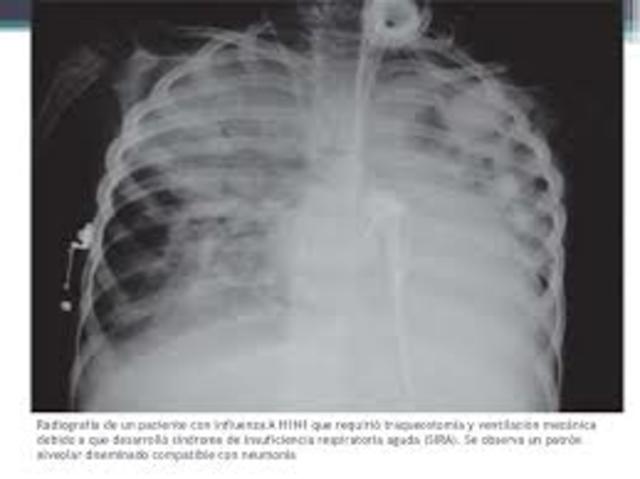

se detectan los primeros casos en el año 2009 en Estados, México y Canadá. Es producida por el virus del H1N1, se denomina porcina por una reorganización de un virus aviar – porcino – humano que generó un virus constituido por genes PA y PB2 aviares, genes PB1 humanos y segmentos de virus de dos linajes distintos circulantes de cerdos.

Estudio publicado en el 2012 por The Lancet Infectious Diseases Online First ofrece las primeras estimaciones globales de mortalidad en el primer año de circulación del virus H1N1 de 2009, las cuales dan una cifra estimada de muertes de entre 151 700 y 575 400 personas en todo el mundo. Esta cifra supera 15 veces la reportada por OMS la cual estaba basada en datos confirmados por laboratorio.